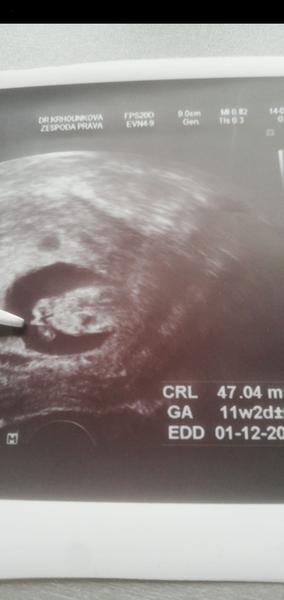

Ahoj holky, čekáme s přítelem první miminko.... Moc se na něj těšíme. Pohlaví nám pan doktor neurčí, musí počkat na další screening ve druhém trimestru. Ale prakticky všichni z rodiny vidí na fotkách z ultrazvuku kluka, co myslíte, může to být kluk??

Ahoj 🙋♀️ máte prosím nějaký tip? Fotka je z 12+2,dekuji 😊